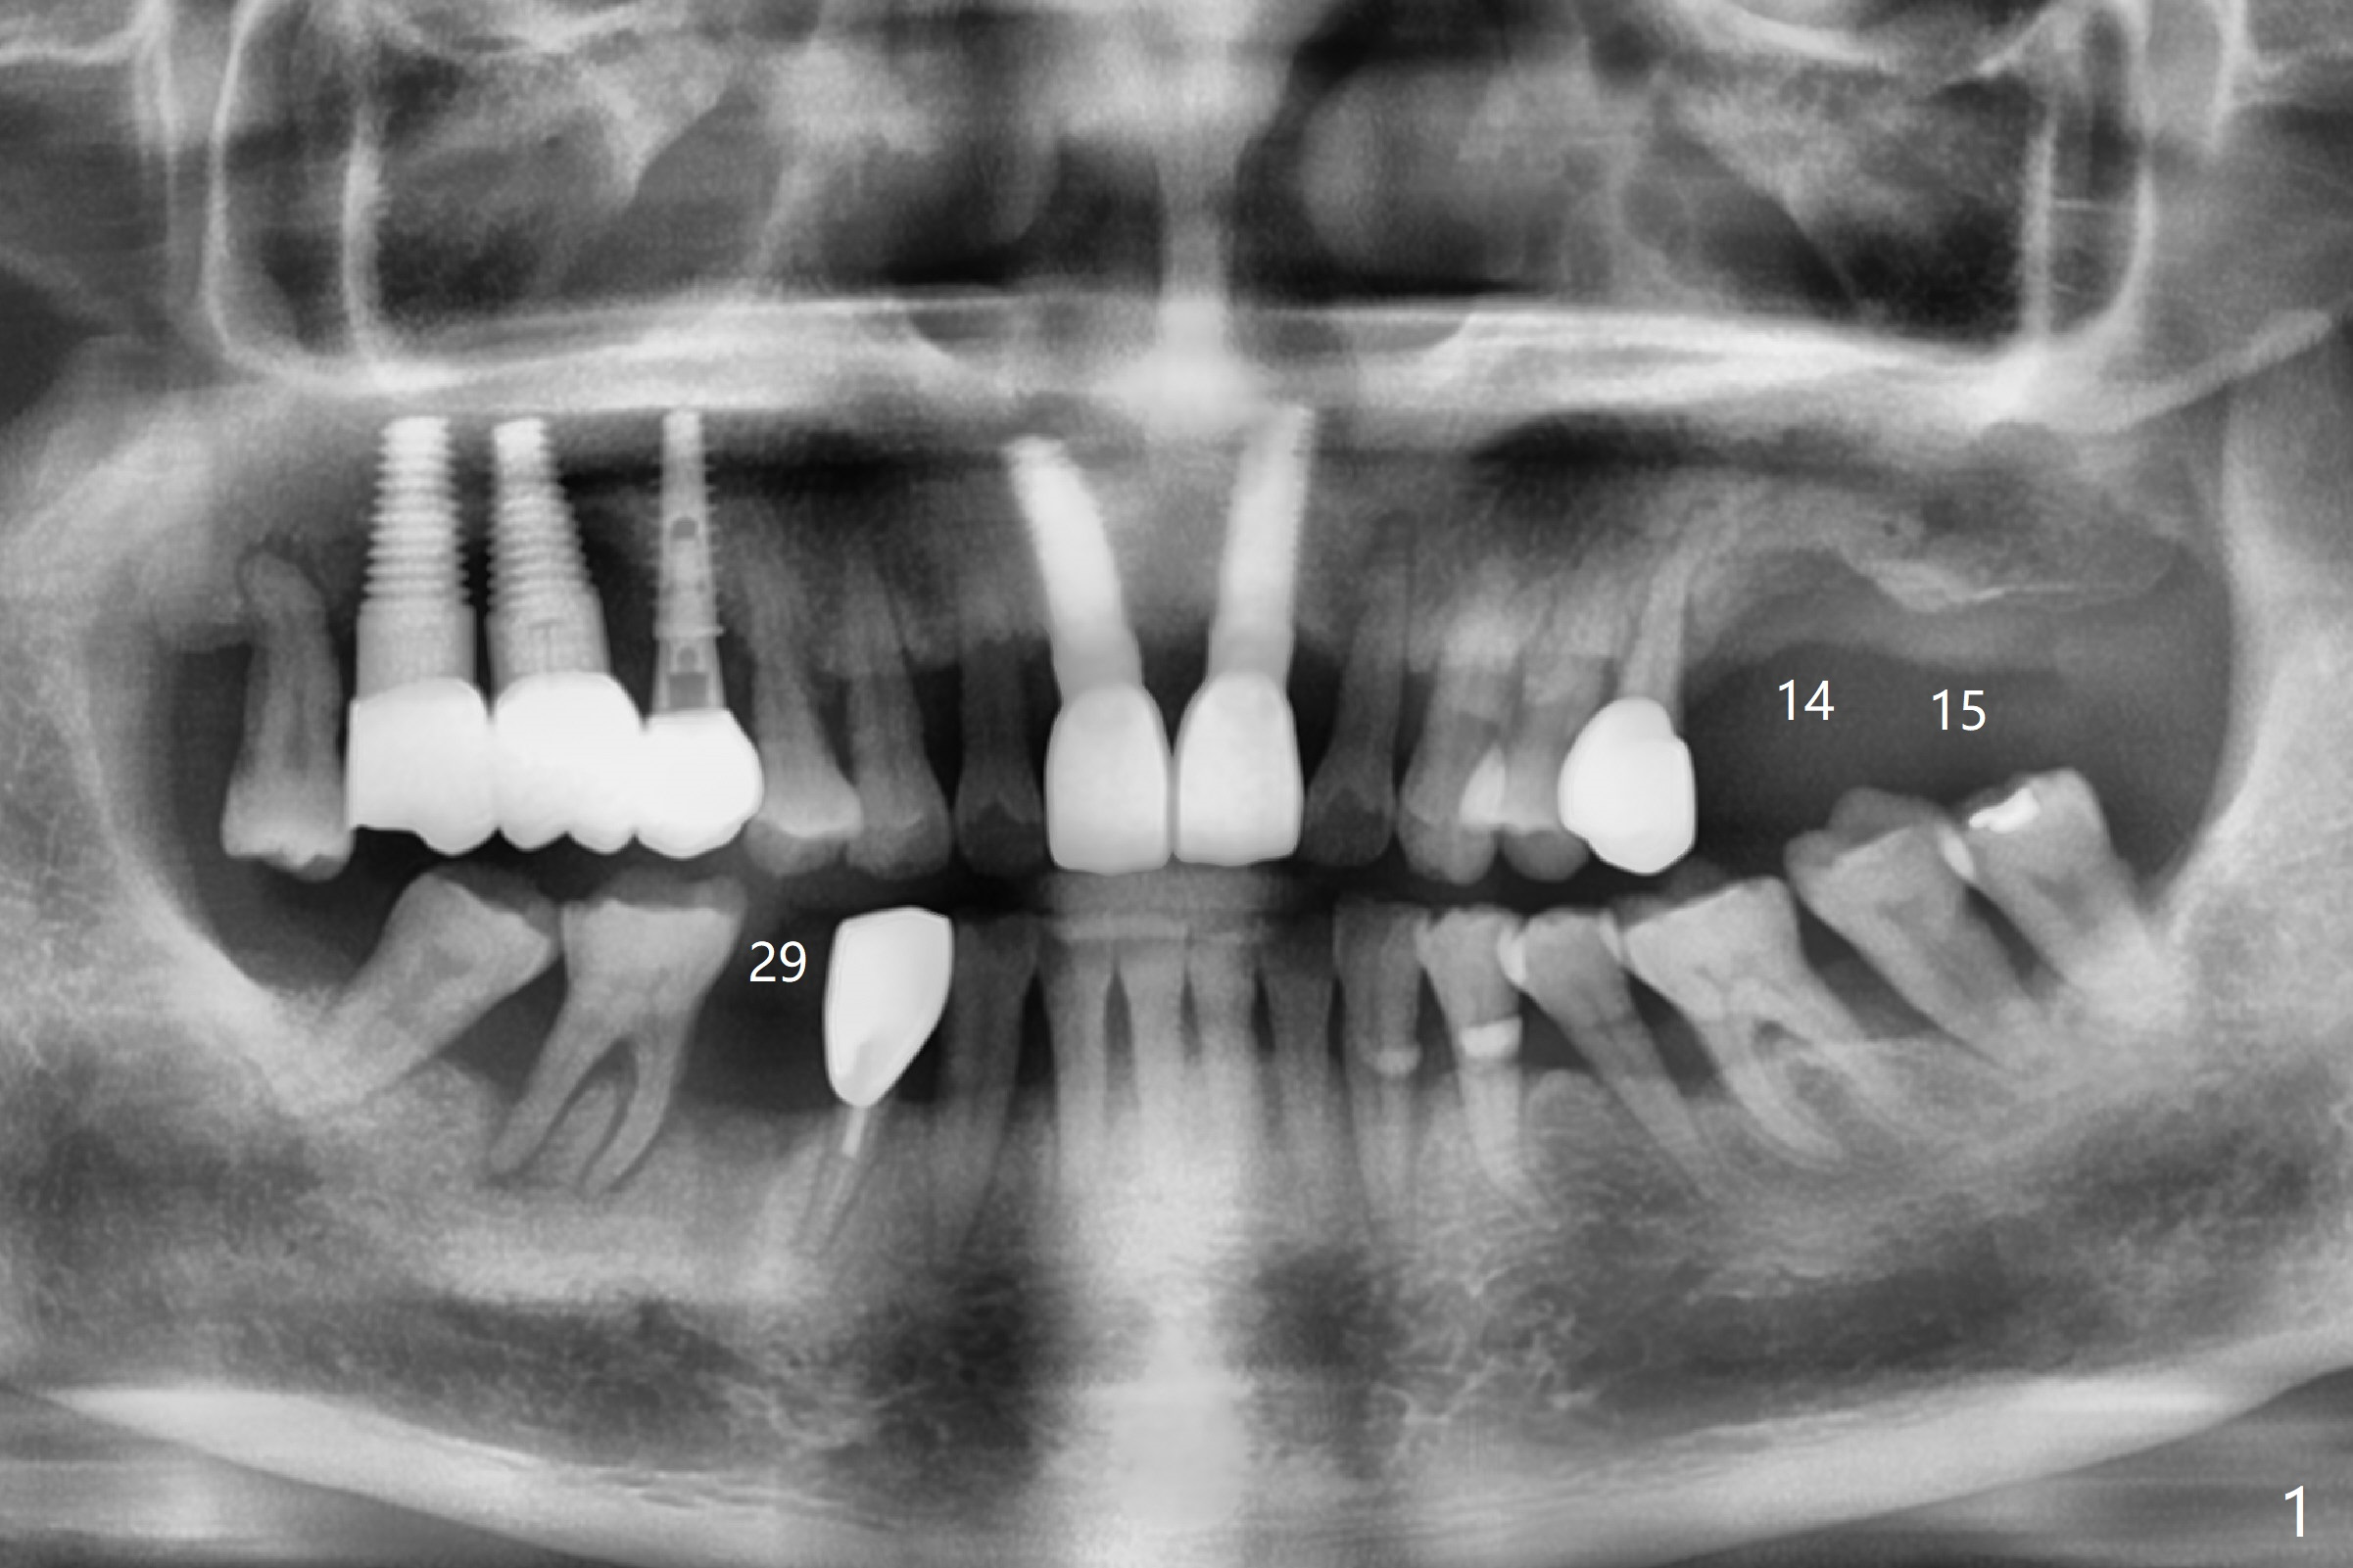

A 48-year-old man returns for implant placement at #14,15 and 29 (5 months post implant removal, 1 year post extraction and 2.5 months post implant removal, respectively, all with bone graft, Fig.1). Since the bone height at #14 and 15 is sufficient and sockets heal, implant placement will be done first (Fig.2,3), as compared to those at #29 (Fig.4). The tooth #18 is periodontally compromised with buccally cross bite (Fig.1); the position of the implant at #15 will be set up normally. When the site of #29 is ready for implant, use a large one (4.5 or 5x8.5 mm; use a dummy one as a tap).